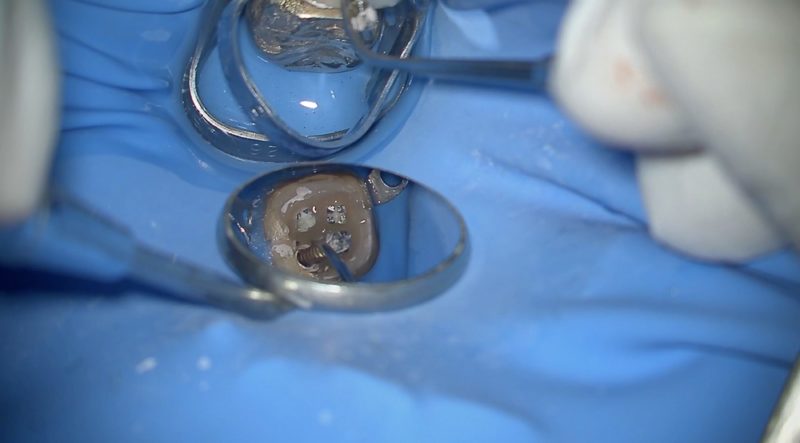

診断をするために歯の中にある全てのもの取り除きます。

歯質を温存するために歯には一切触れずに除去します。

残っているセメント?を全て取り除き、やっと歯の中を観察することができます。

術前診断の通り根管内にクラックがみとめられ、クラックの中に何か詰まっているのが観察できます。

慎重にクラックを削除しながら詰まっているものを除去しました。